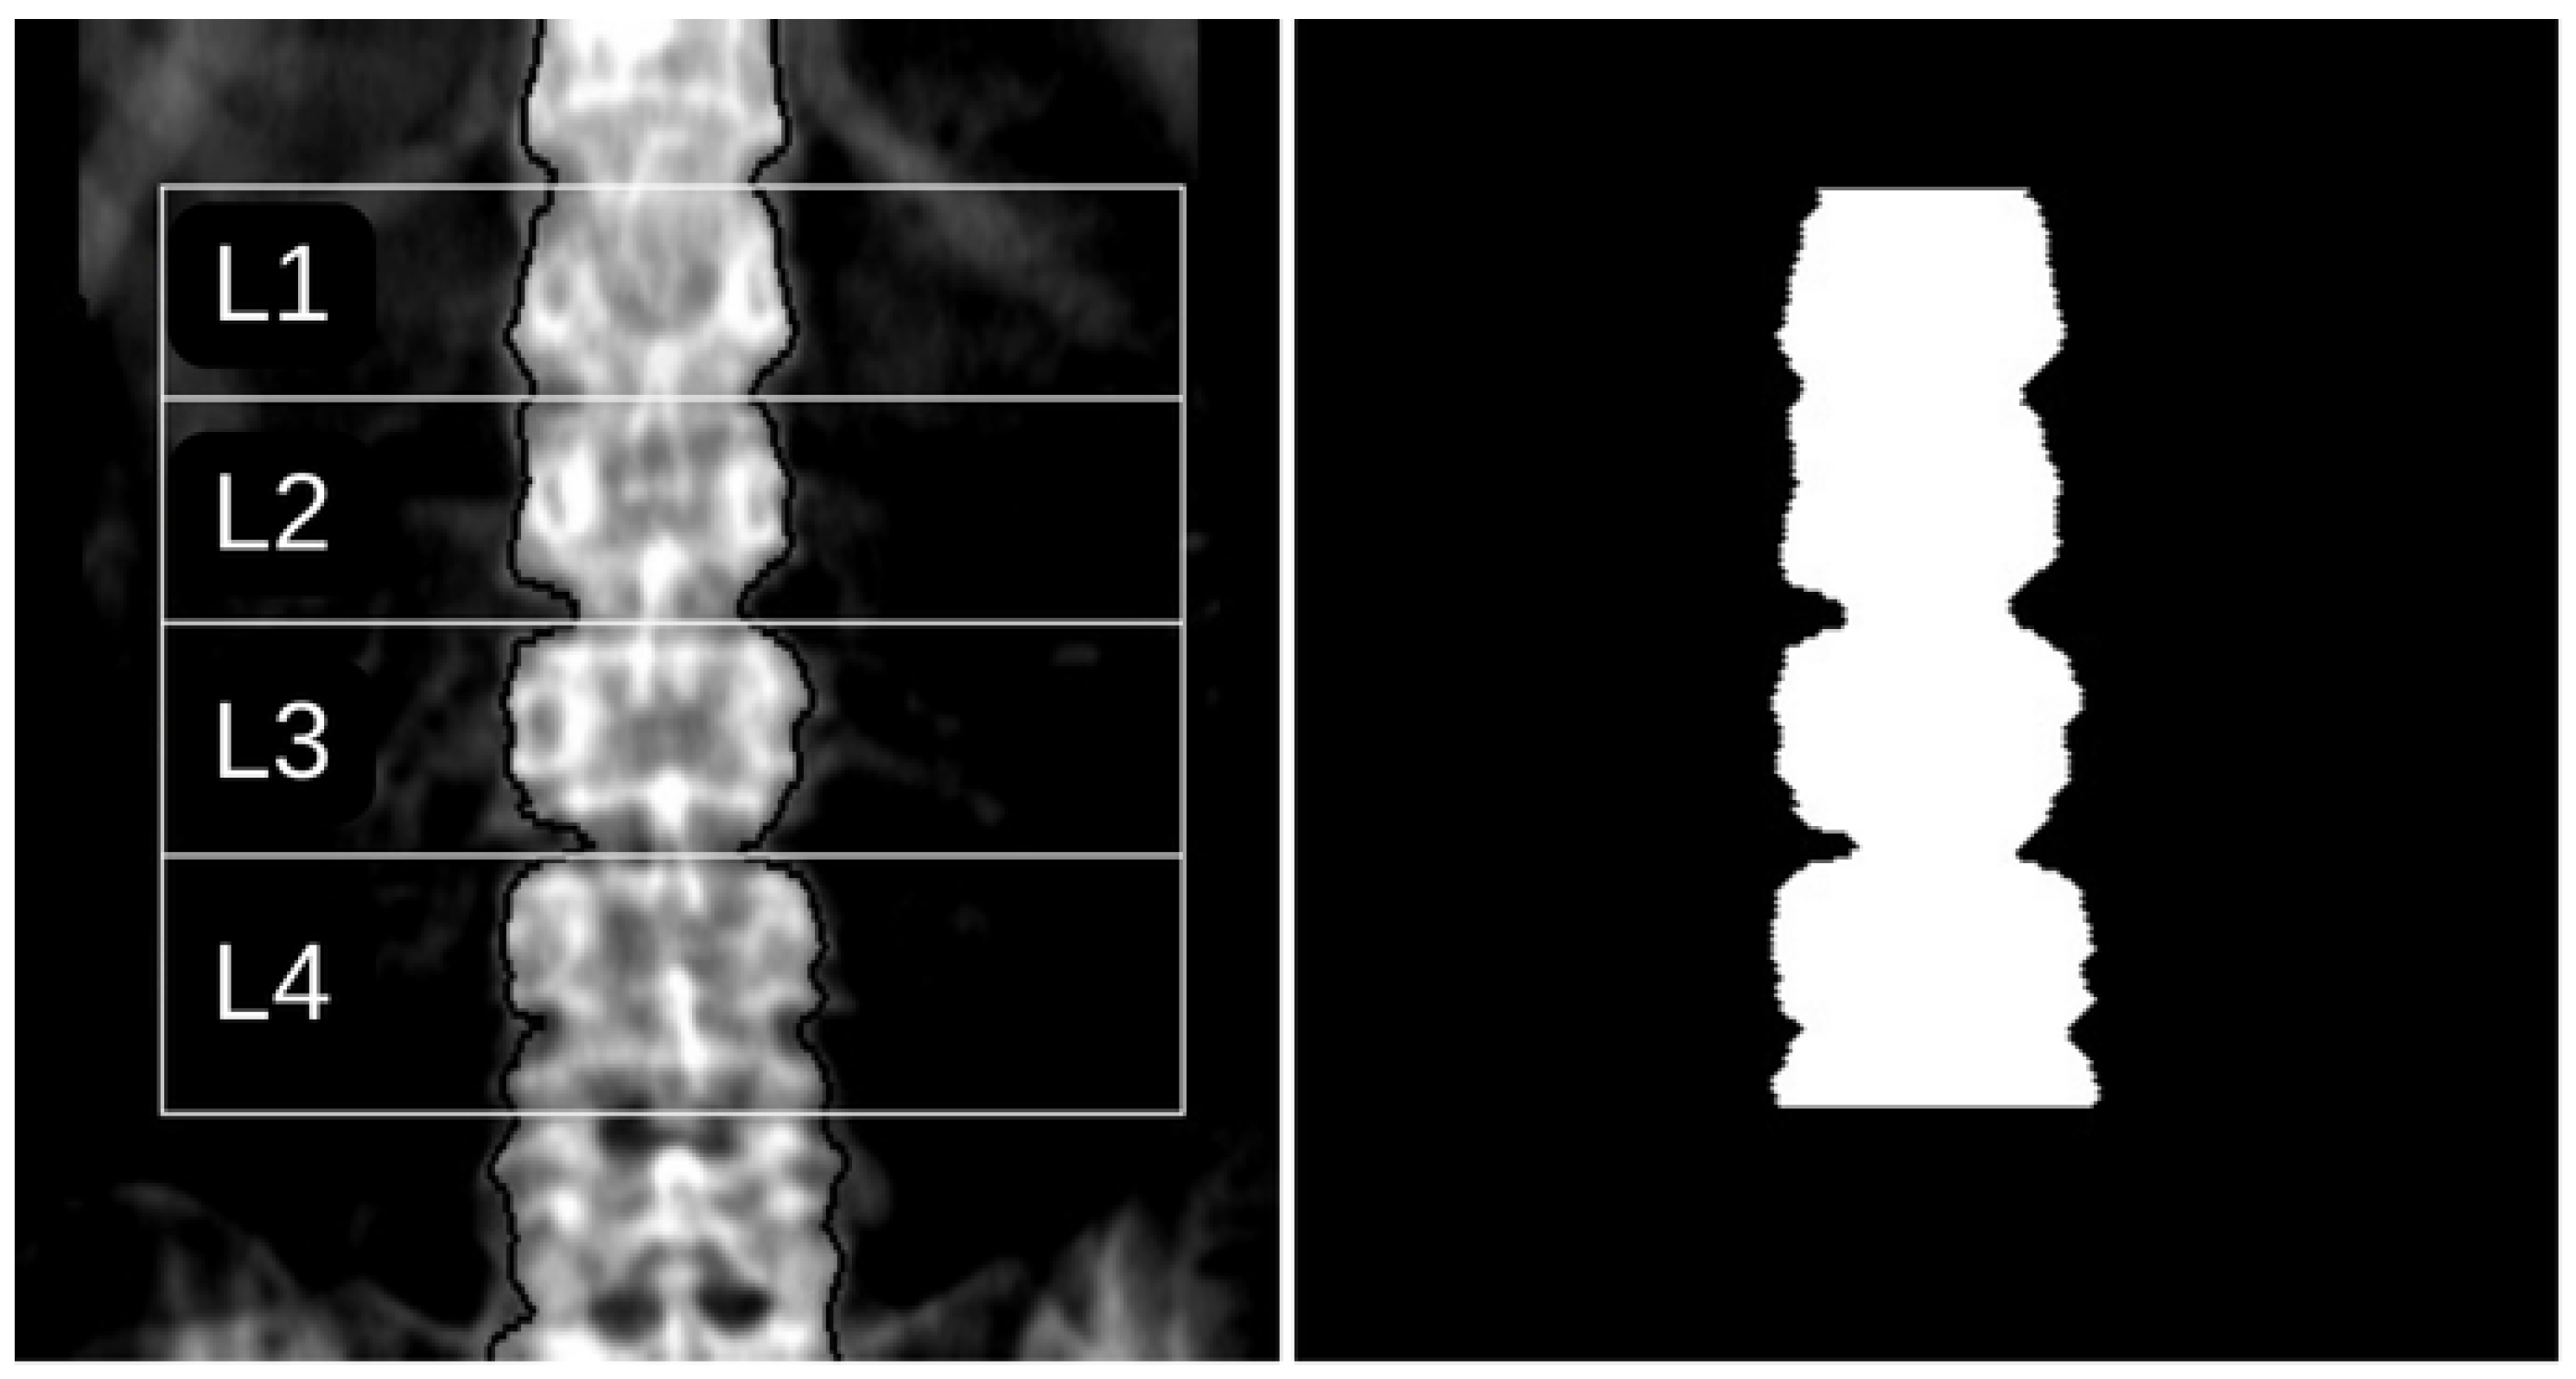

The region of interest (ROI) in this study, corresponding to the lumbar vertebrae L1 to L4, was defined based on the automatic segmentation provided by the DXA equipment’s enCORE v17 software platform. This segmentation was validated by a specialised technician. To ensure consistent results, it is essential to use the same ROI for subsequent analysis. A binary mask was generated using contour detection techniques to replicate the segmentation provided by the software corresponding to the ground truth. Figure 1 illustrates an example of a DXA image with the ROIs defined by the enCORE v17 software and its corresponding binary mask.

The left panel displays a DXA image with ROIs defined by the equipment’s software, and the right panel shows the corresponding automatically generated mask. In the left figure, the lateral contour is delineated by black pixels, while white lines individually divide the four vertebrae of interest.

Finally, in step 4, a totally black image with the same dimensions as the original image is created, and pixels identified in steps 1, 2, and 3 are assigned a white value. The region enclosed by these pixels is also filled with white, defining the ROI in the binary mask, as required by the Pyradiomics library. An example of the resulting binary mask is shown in Figure 1.